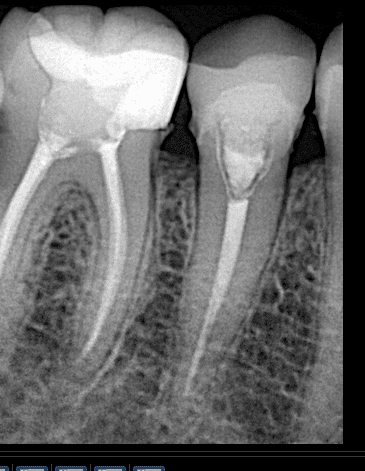

Final x ray

2 weeks later , preparation, macro-core build up

After preparation